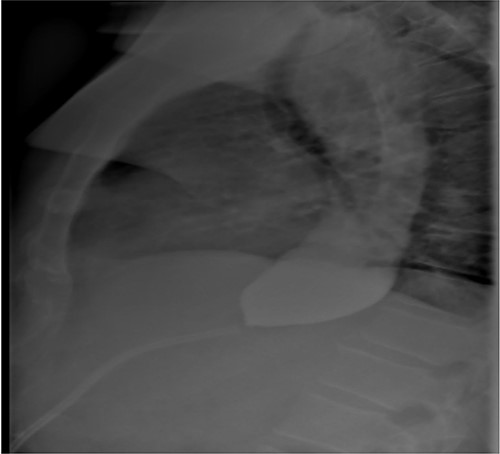

As part of the assessment, computed tomography (CT) coronary angiogram study was performed and it demonstrated a large fluid-filled oesophagus causing partial compression of the left atrium. Barium swallow (Fig. 1A and B), CT chest and abdomen (Fig. 2A and B) and transthoracic echocardiography (TTE) showed a 7.1-cm dilated oesophagus causing left atrial compression and a small hiatal hernia (Fig. 3).

(A) ECHO showing left atrial compression from megaoesophagus during diastole; (B) ECHO showing normal-sized left atrium 3 months after band removal.